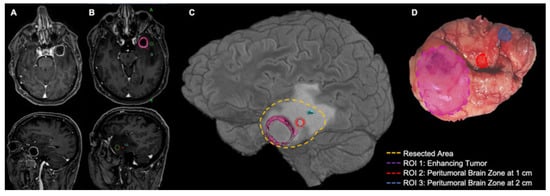

- Lemée, J.-M.; Clavreul, A.; Aubry, M.; Com, E.; De Tayrac, M.; Eliat, P.-A.; Henry, C.; Rousseau, A.; Mosser, J.; Menei, P. Characterizing the peritumoral brain zone in glioblastoma: A multidisciplinary analysis. J. Neuro-Oncol. 2015, 122, 53–61. [Google Scholar] [CrossRef] [PubMed]

- Broggi, G.; Altieri, R.; Barresi, V.; Certo, F.; Barbagallo, G.M.V.; Zanelli, M.; Palicelli, A.; Magro, G.; Caltabiano, R. Histologic Definition of Enhancing Core and FLAIR Hyperintensity Region of Glioblastoma, IDH-Wild Type: A Clinico-Pathologic Study on a Single-Institution Series. Brain Sci. 2023, 13, 248. [Google Scholar] [CrossRef] [PubMed]

- Altieri, R.; Barbagallo, D.; Certo, F.; Broggi, G.; Ragusa, M.; Di Pietro, C.; Caltabiano, R.; Magro, G.; Peschillo, S.; Purrello, M.; et al. Peritumoral Microenvironment in High-Grade Gliomas: From FLAIRectomy to Microglia–Glioma Cross-Talk. Brain Sci. 2021, 11, 200. [Google Scholar] [CrossRef] [PubMed]

- Certo, F.; Altieri, R.; Maione, M.; Schonauer, C.; Sortino, G.; Fiumanò, G.; Tirrò, E.; Massimino, M.; Broggi, G.; Vigneri, P.; et al. FLAIRectomy in Supramarginal Resection of Glioblastoma Correlates with Clinical Outcome and Survival Analysis: A Prospective, Single Institution, Case Series. Oper. Neurosurg. 2021, 20, 151–163. [Google Scholar] [CrossRef]